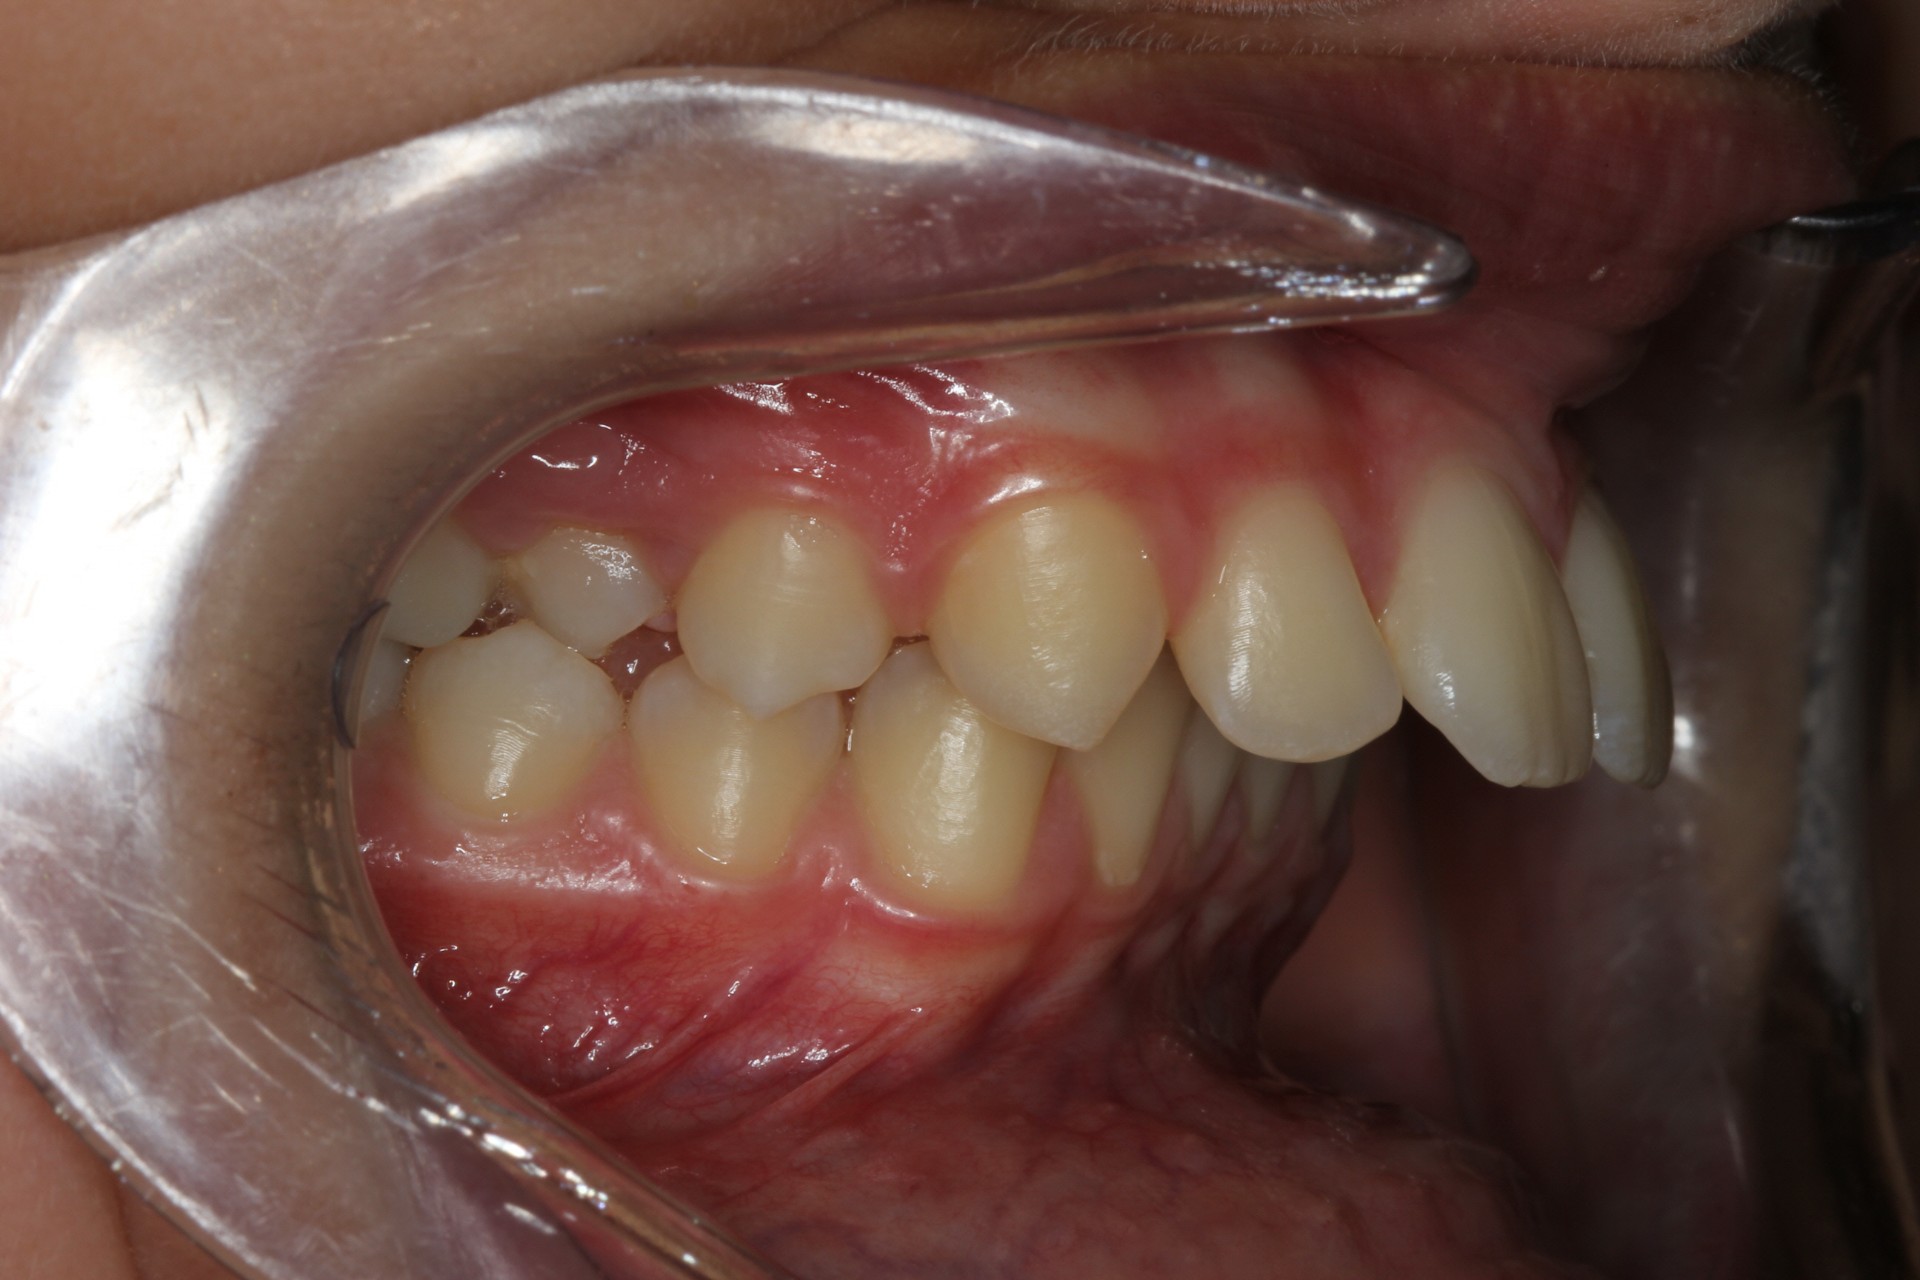

Protruding front teeth – Child case